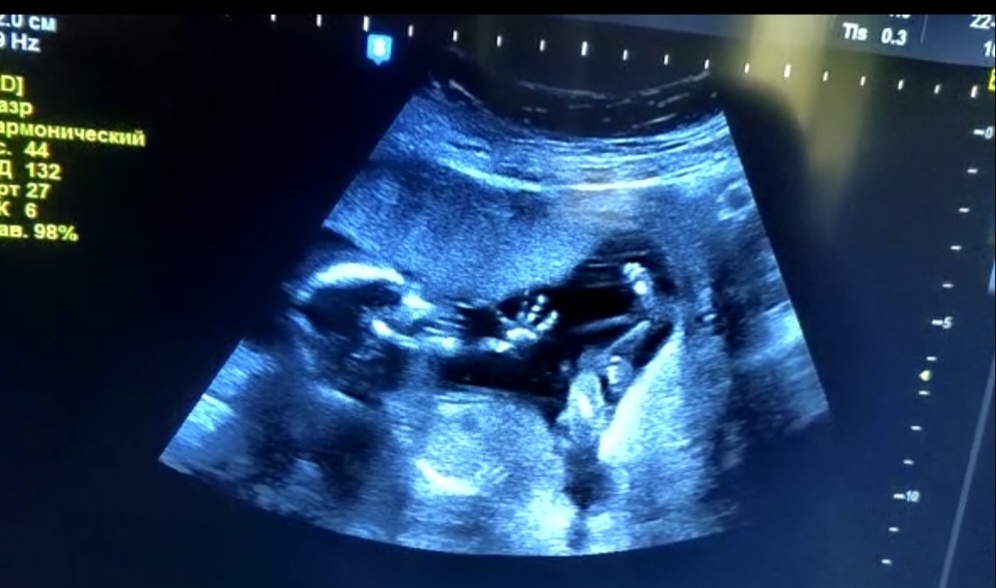

Наша маленькая малышечка❤️ Так мы в 16-17 недель сходили в Центр Мусаловой на определение пола😁😍 Было невероятно круто😍 С мужем понаблюдали за жизнью нашей куколки😍 Наше солнышко, наша кнопочка❤️ Помахала нам ручкой, хотя до этого удачно сосала свой крохотный пальчик😄❤️😍

P.S.: Первое фото это скрин с видео, а вот второе - это уже фото которое сделала узист😁